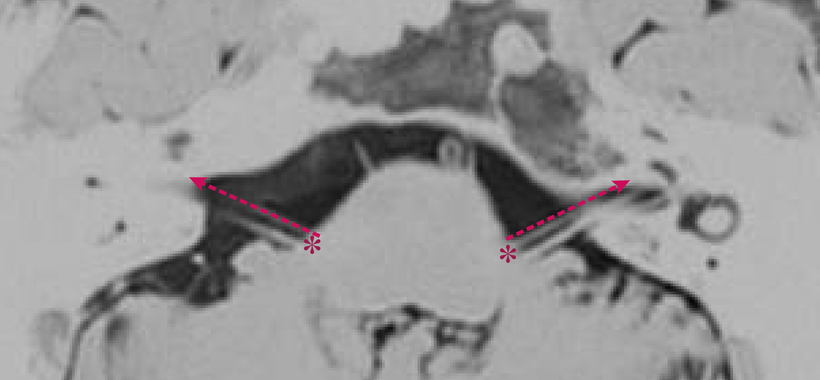

【 顔面痙攣の起きている事がわかるMRI画像-2 】

顔面神経と聴神経との間を走行していた血管(動脈)が、次第に走行を変えていき弓の様な変形をしてしまっている顔面神経(↑)が認められます。これにより、神経根部への血管の走行が認められたり(▲)、顔面神経牽引(点線○)による刺激にて顔面の痙攣が発生します。